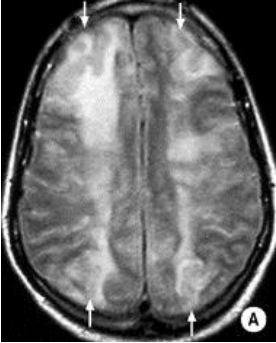

What is the etiology of the MRI image below?

Cardioembolism

• When you see multiple small infarcts like this, think of a shower of emboli dispersed throughout ALL territories of the brain. A cardioembolism is more likely to cause this than say, a carotid artery embolism.

• Cardioembolisms tend to cause larger strokes rather than TIAs - typically a worse prognosis.